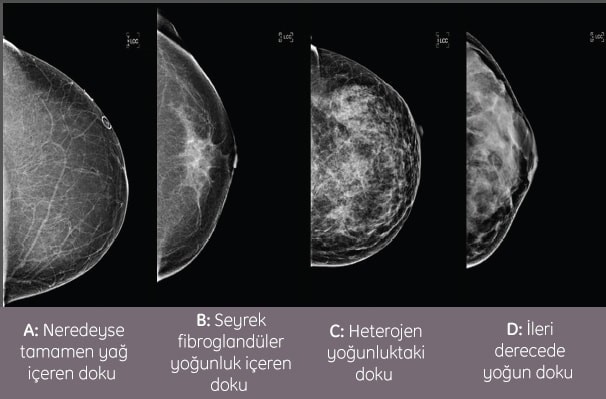

Meme yoğunluğu, memedeki fibröz bağ dokusu miktarına kıyasla yağ dokusu miktarını ifade eden bir ölçüdür. Bağ dokusu, mamografi çekiminde tıpkı bir kanser gibi beyaz görünür ve bu durum bazen doktorların kanseri görememesine neden olabilir. Bazı sağlık uzmanları yoğun meme dokusuna sahip kadınlarda tümör aramanın, kar fırtınasında bir kartopu aramaktan farksız olduğunu söylemektedir.